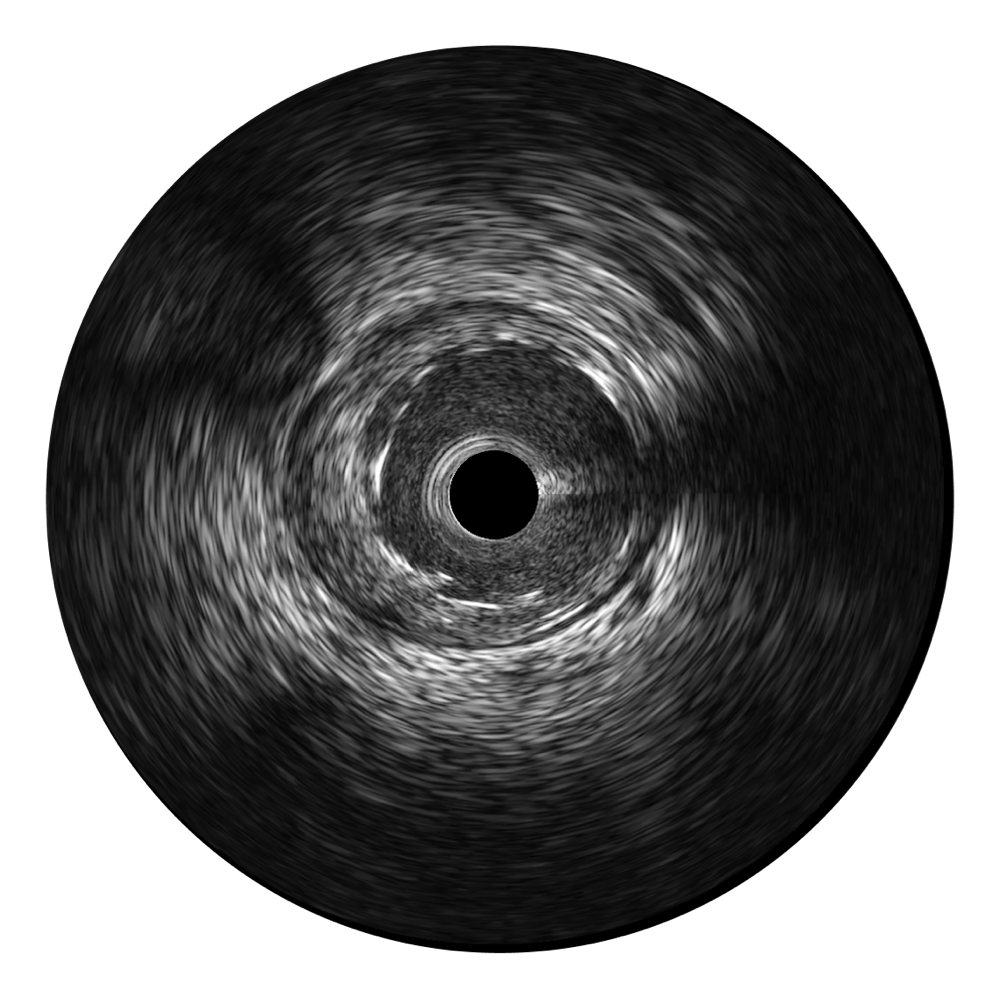

血管内超声(IVUS) 通过对病变程度、性质和累及范围的精确判断,可帮助选择治疗策略和方法,指导介入治疗过程,能够降低主要不良心血管事件,改善预后,在复杂病变介入治疗中用于指导支架置入的优势更为明显。血管内超声(IVUS)已成为精准心血管介入治疗的“金标准”。

宽频成像,兼具高分辨力和更大穿透深度

百老汇电子游戏官网超宽频成像技术覆盖20-80MHz1或20-90MHz2频率范围, 提供优异的分辨力同时也保证充足的穿透深度